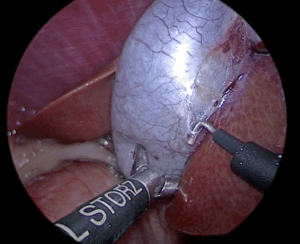

6日続く嘔吐で来院、胆嚢炎を伴う胆嚢粘液嚢腫の所見がみられました。 一般状態の回復を待ち腹腔鏡にて胆嚢摘出と肝臓生検を行いました。経過は良好です。